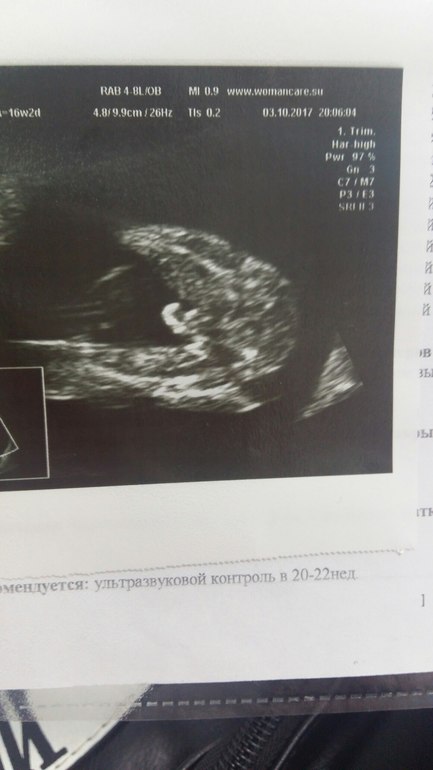

Пол малыша☺️ подтвердилось предположение врача с первого скрининга . Врач не ошиблась. У нас будет сын) Сейчас 17 неделя.